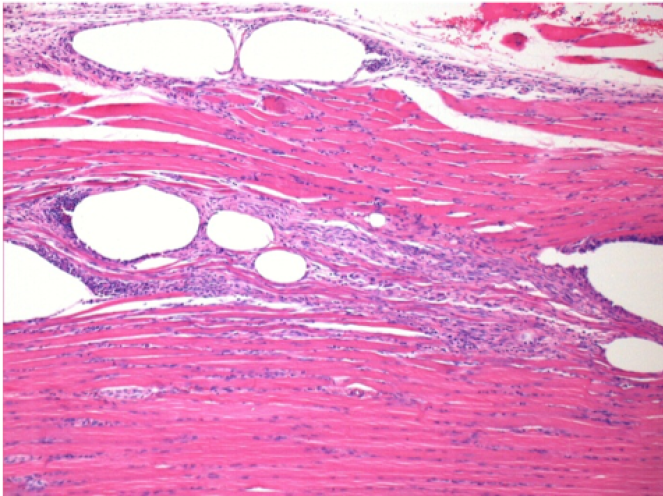

Через 10 днів після ін'єкції Ендопіл 0,1 мл в правий претибіальний м'яз.

Тут можна побачити утворення вакуолей, які оточені лімфоцитами. Вакуолі відрізняються від некрозу тканини. Присутність лімфоцитів пов'язана з проникністю клітинних мембран.